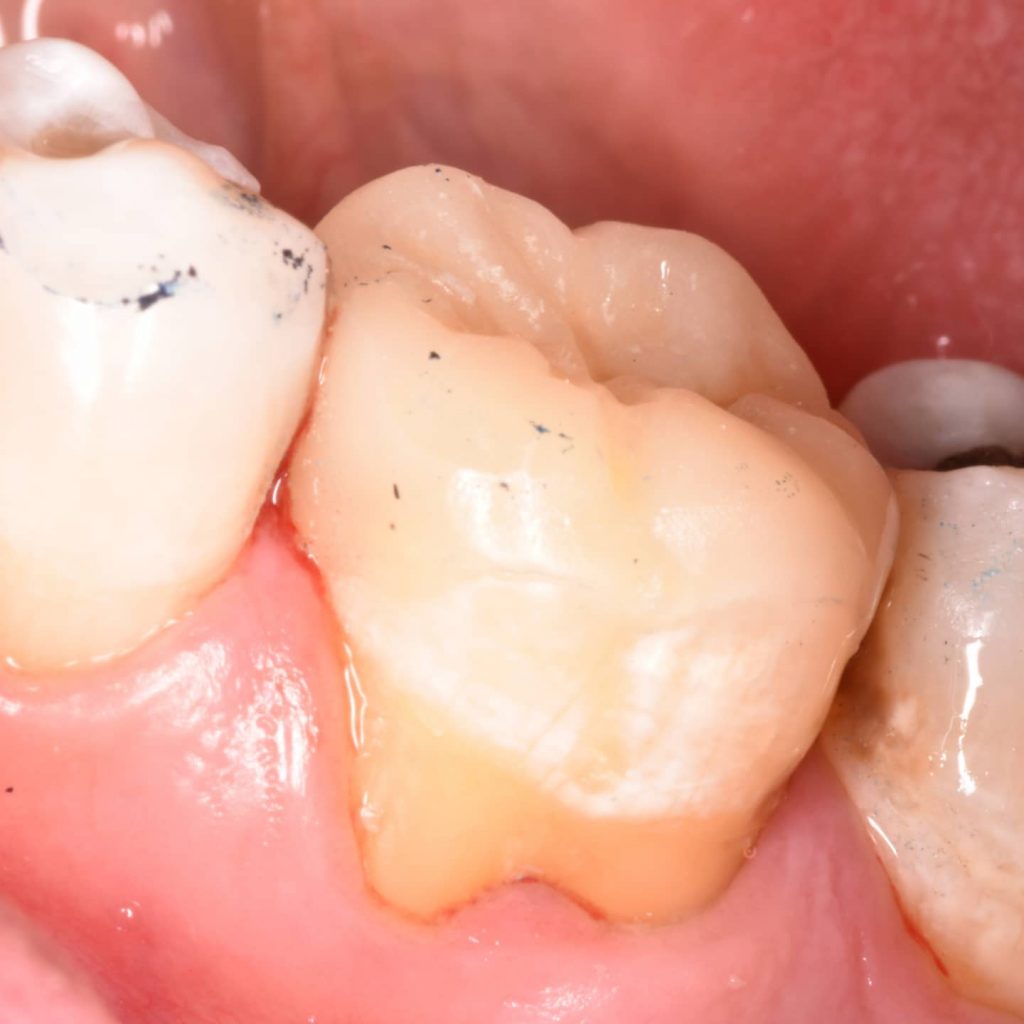

Finshing and polishing

Overlay

After checking the fitness